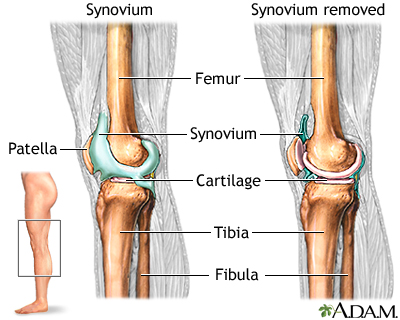

Cartilage covers the end of bones in joints to provide shock absorption during movement. The synovium is the membrane that surrounds the joint and is filled with synovial fluid, which provides nutrients and oxygen to the cartilage.